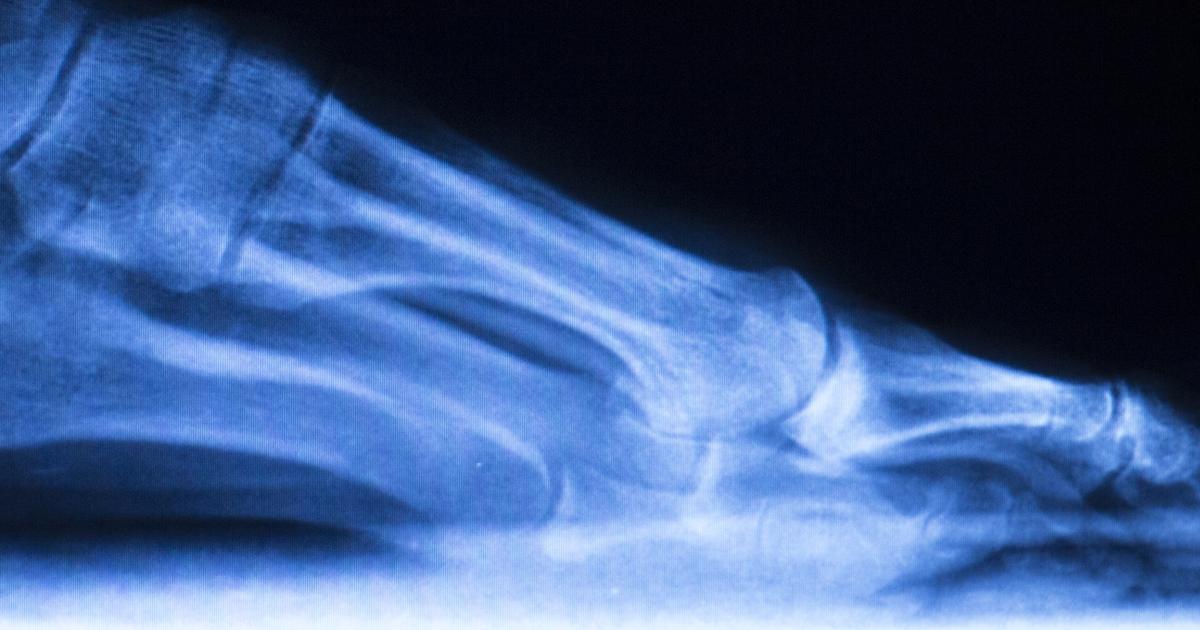

Charcot foot is a complication that occurs in individuals with peripheral neuropathy that involves an inflammatory process affecting the soft tissues of the ankle or foot, bones, and joints. Peripheral neuropathy is a condition characterized by a loss of sensation in the feet from incurred nerve damage in the feet and lower legs. Charcot foot occurs in three stages. Fragmentation and destruction is the first stage and is characterized by small bone fractures, soft tissue swelling, and complete joint destruction. Coalescence, the second stage, is where the body attempts to heal the first stage damage where the bone and joint destruction slows down. Reconstruction is the third stage where the bones and joints of the foot heal themselves up, but not back to their original shape or condition. No further damage is incurred to the foot, but it is left in a weak and deformed state.

Rocker bottom deformity is a common complication that occurs in individuals affected by Charcot foot. This deformity is best characterized by a very pronounced heel bone, and a bulging rounded bottom of the patient's foot. As the joints in the ankle and foot of a Charcot foot patient start to weaken, the joints can become dislocated or collapse entirely. The bones can become fractured without the affected individual knowing about it since their peripheral neuropathy has caused them to have diminished sensation of trauma, pain, and temperature in their foot. The patient keeps walking on the foot and using it like normal, causing the deformity and disorder to progress. The arch of the affected individual's foot caves in, causing it to collapse down under the level of which it would be flattened. This process creates an appearance similar to the leg of a rocking chair. Most individuals who have rocker bottom deformity precipitated from Charcot foot will need surgery to correct the deformity.